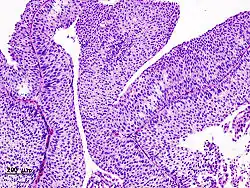

Transitional cell carcinomas are mostly papillary (70%,[2] and 30% non-papillary).[2]

The 1973 WHO grading system for transitional cell carcinomas (papilloma, G1, G2 or G3) is most commonly used despite being superseded by the 2004 WHO[14] grading for papillary types (papillary neoplasm of low malignant potential [PNLMP], low grade, and high grade papillary carcinoma). High-grade carcinoma typically displays more pleomorphism, multiple mitoses, euchromatin and relatively prominent nucleoli, and uneven distribution of nuclei.